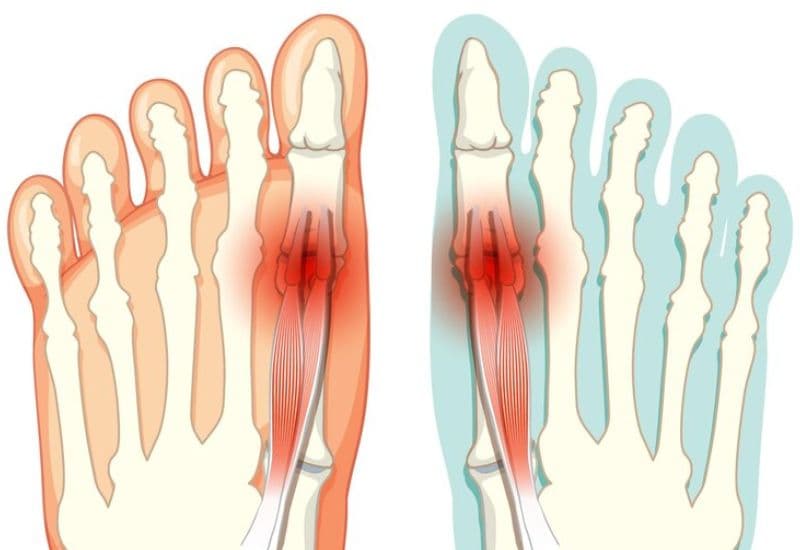

2.2 Sưng tấy, bầm tím

Khu vực xung quanh ngón chân có thể sưng tấy và xuất hiện các vết bầm tím do tổn thương mô mềm xung quanh xương.

2.3 Biến dạng ngón chân

Trong một số trường hợp, ngón chân bị biến dạng rõ rệt, có thể bị uốn cong hoặc lệch khỏi vị trí bình thường.

Khi bị gãy ngón chân người bệnh thường cảm thấy đau đớn tại ngón chân bị gãy, khó cử động, sưng tấy, bầm tím và tê bì.